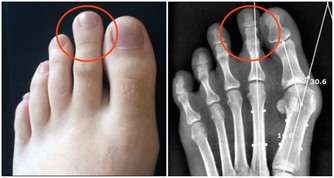

抽筋次數增多。如果不是在運動後或因為受涼而抽筋,那就要注意了,這可能是骨質疏鬆的表現。有些人還會出現足跟疼痛,也必須引起注意。

髖膝關節疼痛。幾乎所有關節都會隨著年紀增大而變得脆弱,特別是髖、膝這兩處關節。如果你發現在下樓梯、蹲下或跳躍時出現不適,甚至腿部有摩擦磨損、卡住動不了的感覺,說明關節已經急需保護了。